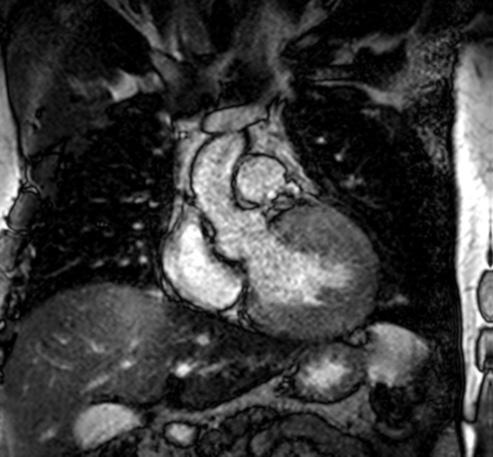

Figure 1: Vista coronal de resonancia magnética cardíaca IVS engrosamiento 3,0cm e infiltración fibrosa septal.

• La resonancia magnética cardíaca

Cardiovascular Disease Fellowship Program, St. Figure 2: Vista sagital de la resonancia magnética cardíaca IVS engrosamiento de 3,0 cm e infiltración fibrosa septal.

posterior mostró un engrosamiento del tabique interventricular de 3,0 cm, así como una infiltración fibrosa del tabique confirmando el diagnóstico de MCH.

Figure 3: Vista axial de resonancia magnética cardíaca IVS engrosamiento 3.0cm e infiltración fibrosa septal.